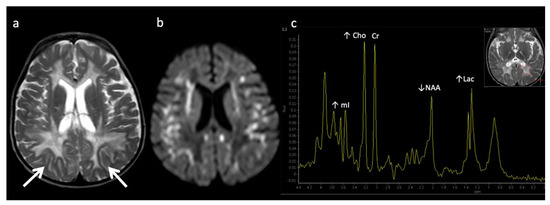

X-linked Adrenoleukodystrophy (ALD) (Figure 12): This peroxisomal disorder is due to a defect in oxidation of long-chain fatty acids resulting in their accumulation. Lesions usually initiate in the callosal splenium and spread into the forceps major, projectional fibers, and auditory and visual pathway; however, in a minority of cases, they may begin in the callosal genu and extend into the forceps minor and beyond [3,41]. Laminated zones of signal alteration in the involved cerebral areas are characteristic, with reduced diffusion and post-contrast enhancement during active demyelination and inflammation, The addition of X-ALD to newborn screen testing has brought about pre-symptomatic MR screening; these scans require careful scrutiny for early/mild changes with special attention to the corpus callosum [42]. Boys with X-ALD should be monitored with serial MRIs based on consensus guidelines [43]. MRS demonstrates decreased NAA and elevated Cho and mI, findings that can improve after successful stem cell transplant [44,45].

Figure 12.

Six-year-old male with X-linked Adrenoleukodystrophy (ALD). (a) Axial T2 and (b) DWI images reveal confluent T2 hyperintensity (a) and reduced diffusion (b) involving the callosal splenium and forceps major/peri-trigonal white matter (white arrows) with sparing of subcortical U-fibers. The pattern of involvement has a postero-anterior and centrifugal pattern. A zonal pattern of signal alteration with mixed diffusion abnormalities indicates acute on chronic demyelination related injury. (c) SV-MRS of the left periatrial white matter reveals decreased NAA (neuronal loss, decreased neuronal-axonal integrity, and/or decreased production), elevated Cho (increased membrane turnover), increased mI (neuroinflammation marker), and increased Lac (anaerobic metabolism).